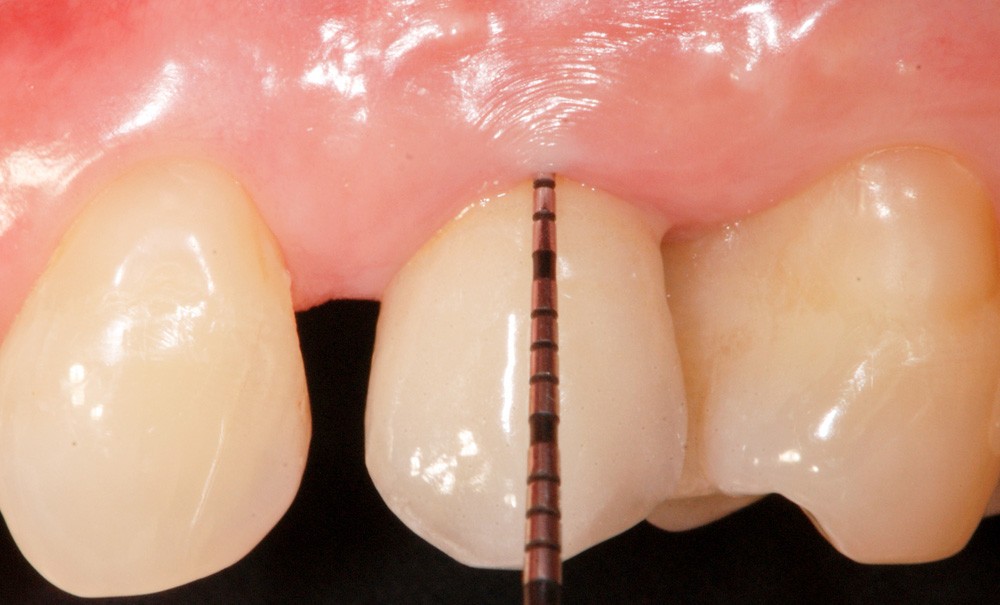

Les critères qui permettent de diagnostiquer une péri-implantite sont aujourd’hui bien établis, les voici rappelés : signes cliniques d’une inflammation péri-implantaire (gonflement, rougeur, saignement au sondage et/ou suppuration) (fig. 1a), perte osseuse péri-implantaire au-delà de celle constatée après la cicatrisation « initiale » (fig. 1b), augmentation de la profondeur de poche au sondage en comparaison de la profondeur de poche identifiée lors de la mise en place de la restauration prothétique [2, 23]. En l’absence de documents radiographiques préexistants, une perte osseuse supérieure ou égale à 3 mm en association avec un saignement au sondage et une profondeur de poche au sondage supérieure ou égale à 6 mm permet également de poser le diagnostic de péri-implantite [23].